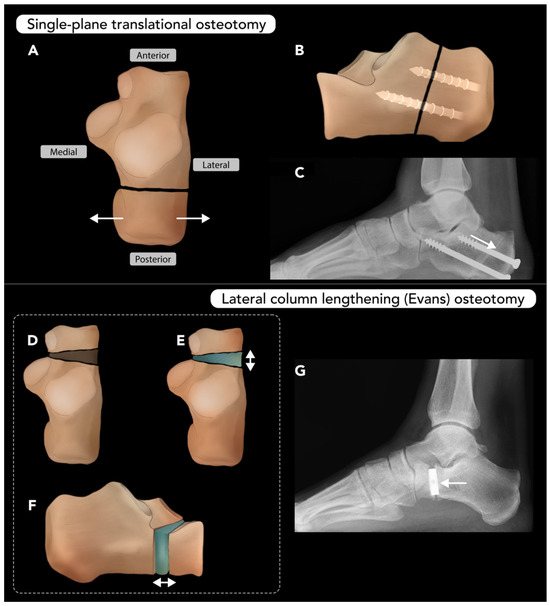

2.3.3. Calcaneal Osteotomy

- Meyr, A.J.; Sansosti, L.E.; Ali, S. A pictorial review of reconstructive foot and ankle surgery: Evaluation and intervention of the flatfoot deformity. J. Radiol. Case Rep. 2017, 11, 26. [Google Scholar] [CrossRef] [PubMed]

- Soltanolkotabi, M.; Mallory, C.; Allen, H.; Chan, B.Y.; Mills, M.K.; Leake, R.L. Postoperative Findings of Common Foot and Ankle Surgeries: An Imaging Review. Diagnostics 2022, 12, 1090. [Google Scholar] [CrossRef]

- Tennant, J.N.; Carmont, M.; Phisitkul, P. Calcaneus osteotomy. Curr. Rev. Musculoskelet. Med. 2014, 7, 271–276. [Google Scholar] [CrossRef]